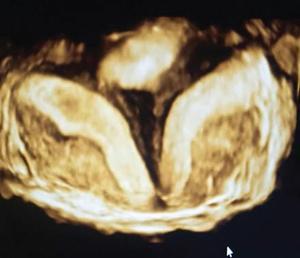

MÜLLERIAN DUCT ANOMALIES Rajani Gorantla Müllerian ducts are a pair of tubular structures that give rise to uterus, cervix, fallopian tubes and upper two-thirds of vagina. Disruption or failure of normal development can result in occurrence of Müllerian duct anomalies (MDAs). These are commonly associated with other congenital anomalies of urinary tract and ovaries due to the close relationship between the development of mesonephric and paramesonephric ducts; few patients also have associated skeletal system anomalies. The prevalence of MDAs in an unselected population was 5.5%; 8% among the infertile women, 12.3% in women with a history of recurrent pregnancy loss and 24.5% in women with miscarriage and infertility. Most of the patients with MDAs are asymptomatic and found incidentally on imaging for any other gynaecological problems, in evaluation of a patient with renal, skeletal or abdominal wall abnormalities. In symptomatic women, complains are related to the type, severity, obstructive anomaly or nonobstructive anomaly. The symptoms can be obstetric or gynaecological related, includes recurrent spontaneous abortions, infertility, preterm labour, intrauterine growth restriction and abnormal foetal lie. Few adolescent girls may present with primary amenorrhoea, hypomenorrhoea, abnormal vaginal bleeding, cyclical pain and mass. Rarely they can present with pelvic inflammatory disease with abnormal vaginal discharge, dyspareunia and urinary tract infections. The female reproductive system develops from a pair of Müllerian or paramesonephric ducts, urogenital sinus and vaginal plate. The ovaries develop separately from the primordial ridge. It is of great importance to understand the normal stages of development, as failure or interruption of any of these stages can lead to a simple to complex spectrum of anomalies. The three stages of Müllerian duct development include: At 6–10 weeks of gestation age, two paired Müllerian ducts and Wolffian ducts formation occurs. When Y chromosome factor (testicular determining factor) is absent, the Wolffian ducts undergo degeneration. The Müllerian ducts further elongate caudally and cross the Wolffian ducts to fuse in the midline. At 10–13 weeks of gestation age, caudal and lateral fusion of the two Müllerian ducts forms primitive uterovaginal canal, which is possessed of solid tissue initially located side by side and further internal canalization leads to the formation of two channels/canals divided by a septum. At this stage, there is reabsorption of the caudal septum and forms single cervical canal and vagina lumen. In around 15–20 weeks of gestation age, complete resorption of the septum takes place in a caudocranial direction from the isthmus to fundus and development of single endometrial cavity results. The fused caudal part of Müllerian ducts gives rise to the uterus, cervix and upper two-thirds of vagina; the unfused cranial part forms the fallopian tubes (Fig. 11.14.1.1). The lower vagina develops from the urogenital sinus, which is separated from the rectum by urorectal septum around 7 weeks of gestation age. The primitive uterovaginal canal embeds into the dorsal wall of urogenital sinus and forms Muller’s tubercle. Around 13 weeks of gestation, two solid masses known as sinovaginal bulbs originate from the upper part of the Muller’s tubercle, further proliferate into the caudal end of the uterovaginal canal to become a solid vaginal plate. Later canalization or degeneration of the central cells of the vaginal plate forms the lower vagina, which is usually completed by 20 weeks’ gestation. The vertical fusion of the upper and lower vagina occurs with resorption of tissue in between and forms single vaginal cavity (Fig. 11.14.1.2). The vaginal lumen is separated from the urogenital sinus by the hymenal membrane. Just before birth, the hymen normally ruptures due to retrogression of the central epithelial cells. However, a thin fold of mucous membrane persists around the vaginal introitus. The ovaries develop separately from migration of primordial germ cells to the genital ridge. Ureteric buds develop separately and concurrently. So renal anomalies are most commonly associated with MDAs with an association of 30%–50%. Various classification systems have been proposed over the past several decades to describe MDAs. Ideally, same classification system needs to be followed by a gynaecologist, surgeon and radiologist for better communication. Buttram and Gibbons classification was suggested in 1979, and it was based upon the level of failure in normal development and segregate the anomalies into groups with similar clinical manifestations, treatment, and prognosis for foetal salvage. According to Buttram and Gibbons, the uterine anomalies were classified into six classes as described in Table 11.14.1.1. The drawback is the lack of classification of vaginal and other anomalies separately. The ASRM (previously the American Fertility Society – AFS) classification system is the most widely accepted classification worldwide over the past years and was introduced in 1988. According to this classification, MDAs are classified into seven classes (class I to class VII) as mentioned in Table 11.14.1.2. However, several limitations have been described by Grimbizis and Campo in 2010 (Fig. 11.14.1.3). The drawbacks of the ASRM classification system are as follows: Hence in 2016, an updated classification of uterine septum, that is ASRM-2016 was proposed and officially approved morphometric criteria are given for distinguishing between septate, normal/arcuate and bicornuate uteri (Table 11.14.1.3). The VCUAM classification was proposed in the year 2005. The main concern is to provide a simple, systematic, clinical classification in addition to providing a precise reflection of the entire malformation. The female genital organs were divided into the following subgroups in accordance with the anatomy: vagina (V), cervix (C), uterus (U) and adnexa (A). Associated malformations were assigned to a subgroup (M) relative to each specific organ. The disadvantage is due to its inherent complexity, and more than 56,700 individual combinations of anomalies are possible. ESHRE and ESGE established a common working group named CONgenital UTerine Anomalies (CONUTA) in order to devise an improved classification system (Table 11.14.1.4). It was published in 2013. Anatomy is the basis for systemic categorization of the MDAs. The subclasses are divided by the different degrees of uterine deformity and their clinical significance (Fig. 11.14.1.4). Cervical and vaginal anomalies are classified into independent supplementary subclasses (Figs. 11.14.1.5–11.14.1.6). For most of the clinicians, it helped as starting point for the development of guidelines for their diagnosis and treatment. The malformations are graded according to severity, U0–U5, C0–C4 and V0–V4, with U5, C4 and V4 being more severe. Class U3 incorporates bicorporeal fusion defects (didelphys and bicornuate) as this was considered as a more functional mode of classification. Arcuate uterus was not included separately, but this is categorized under normal variant into class U1c. Recent studies have demonstrated that the ESHRE/ESGE system provides an effective and comprehensive classification for almost all the currently known MDAs and overcomes the limits of previous classifications. However, there is a relative overdiagnosis of septate uterus with the application of ESHRE–ESGE criteria has been reported and which potentially might lead to unnecessary surgical overtreatment. C0 C1 C2 Normal cervix Septate cervix Double ‘normal’ cervix C3 C4 Unilateral cervical aplasia Cervical aplasia U4 V0 V1 V2 V3 Normal vagina Longitudinal nonobstructing vaginal septum Longitudinal obstructing vaginal septum Transverse vaginal septum and/or imperforate hymen V4 Vaginal aplasia C MDAs’ characterization and classification is of great significance, as the treatment is determined by the type and severity of abnormality. The various imaging modalities available include: HSG was the most recognized imaging modality, earlier to the development of the ultrasonography (USG) and MRI. It is an invasive fluoroscopic-guided procedure for uterine and tubal assessment, and is performed during the midproliferative phase of the cycle, ideally between days 7 and 10 of the cycle when endometrium is thin. Fluoroscopic spot images obtained to evaluate uterine configuration, uterine filling defects and fallopian tube patency. HSG allows evaluation of only the component of the uterine cavity that communicates with the cervix. The anatomic information about myometrium and external fundal contour will not be provided by HSG. The diagnostic criteria used to diagnose MDAs on HSG include: HSG findings of different MDAs are described in Table 11.14.1.5 and Fig. 11.14.1.10. Virtual HSG is a noninvasive technique performed by using a computed tomography (CT) scanner, done 45 s after the contrast material instillation begins. Contraindications are similar to those for HSG and include pregnancy and active pelvic infection. There is no necessity for retraction of the uterus or manipulation of the cervix. The procedure is quick, easy and prophylactic administration of antibiotics is not required. The use of a power injector helps to ensure a steady low pressure of instillation. The procedure is less painful, more comfortable and easily tolerated by patients than conventional HSG. Radiation exposure sometimes requires cervical clamping, which may result in complications such as bleeding and infection. Transabdominal pelvic ultrasound can diagnose uterine anomalies with accuracy rate of 47%. Two-dimensional transvaginal ultrasound (TVUS) has high sensitivity and specificity than transabdominal study and provided some information about external and internal fundal contours. The detection rate is high if the scan is performed in secretory phase due to better visualization of endometrium. Three-dimensional USG shows great accuracy than 2D USG in evaluation of the uterine morphology. The technique of 3D USG varies with different vendors. It displays both the external and internal fundal contours and lower uterine segment by acquisition of single coronal view of uterus (c-view) (Fig. 11.14.1.11). The only disadvantage is that it is transvaginal study and shall not be done in paediatric age group and sexually inactive women. Three-dimensional TVUS has become the first line of screening tool in most of the infertility clinics as it is noninvasive, faster, repeatable, allows storage of volume data and has multiplanar capability for systematic evaluation of the uterine and cervical cavities. The salient features of various Müllerian anomalies on 3D USG are described in Table 11.14.1.6 with images. Three-dimensional ultrasound is combined with sonosalpingography in this technique and provides better delineation of the uterine morphology. It is a less invasive procedure done in proliferative phase with instillation of saline into the uterine cavity and assessment of the uterus will be done. MRI is a universally accepted imaging modality in the documentation of MDAs and accuracy rate of 100% have been reported. MRI provides excellent delineation of both the internal and external uterine anatomies. T2-weighted (T2W) images are the mainstay of pelvic imaging and are performed without fat suppression. T1-weighted (T1W) images are mainly for the haemorrhagic content. The disadvantages of MRI include time-consuming procedure, not cost-effective, large body habitus, pacemakers, recent surgical history and claustrophobia. The current and proposed MRI protocol given by the European Society of Urology (ESUR-MRI protocol) intends a dedicated evaluation of MDAs as mentioned below (Fig. 11.14.1.12): Vaginal anomalies can be accurately diagnosed with the prior administration of the ultrasound gel, to distend vagina (Fig. 11.14.1.13). It will help in better diagnosis of complex vaginal anomalies, like vaginal septations or vaginal duplication. The normal MRI appearance of uterocervical canal and vagina are shown in Fig. 11.14.1.14. Uterine aplasia/hypoplasia/agenesis is class 1 MDA according to ASRM classification and U5 uterine anomaly according to ESHRE classification. It is a formation defect of the paramesonephric ducts with complete or segmental agenesis of uterus and vagina. The incidence rate is around 10%–15% of all MDAs and considered as the most severe form of uterine anomaly. Most of them have complete uterovaginal agenesis with no single completely developed uterine cavity and are associated with Mayer–Rokitansky–Küster–Hauser syndrome (MRKHS). Two types of this syndrome are depicted. The typical form or type A represents the absence or remnants of the uterus, cervix, upper two-thirds of vagina with normal ovaries and fallopian tube (Fig. 11.14.1.15). The atypical form or type B is associated with the abnormalities of the ovaries, fallopian tubes and genitourinary system (Fig. 11.14.1.16). In a few cases (approximately 10%), unilateral or bilateral uterine remnants and with or without endometrial cavity will be seen (Fig. 11.14.1.17). Most of them present with primary amenorrhoea due to complete uterovaginal agenesis and manifest as MRKHS. These patients have normal secondary sexual characteristics due to the preserved normal ovarian function and phenotype. If uterine remnants with functional cavity is present, will present with cyclical pain along with amenorrhoea due to cryptomenorrhoea and haematometra. USG is the first modality for identification of these anomalies, absence of uterus with normal ovaries is diagnostic. But, it is difficult to locate the uterine remnants and cavity due to small acoustic window. MRI is the gold standard and it classifies into uterovaginal agenesis and hypoplasia. If hypoplasia is identified, sagittal and axial sections are taken. These remnants are seen as T2 hypointense tubular structures, located in close relation to ovaries in the adnexa. Once we identify the uterine remnants, it is important to look for the functional endometrial cavity. These will have reduced endometrial and myometrial width. MRI can easily delineate the zonal anatomy due to its high soft tissue contrast resolution. The management of Müllerian agenesis consists of counselling for the patient and her parents. Some patients with MRKHS opt for creation of neovagina for normal sexual life. Various techniques are available. In the presence of a functional Müllerian remnant, regardless of whether it is communicating or not, medical suppression of menses can be initiated and should be followed by laparoscopic removal of the hypoplastic remnant. Unicornuate uterus or hemiuterus is defined as the unilateral uterine development and the contralateral Müllerian duct could be either partially formed or absent. It is a formation defect and the necessity to classify it in a different class than that of uterine agenesis, which is also a formation defect, is due to the existence of a fully developed functional uterine hemicavity. It is considered as class II anomaly according to ASRM classification and class U4 according to ESHRE classification. The frequency rate is around 20% of MDAs. Renal anomalies most often occur in association with unicornuate uterus and usually on the same side of uterine agenesis. Further unicornuate uterus is divided into two subclasses depending on the presence or absence of a functional rudimentary cavity in ESHRE classification: In ASRM classification, unicornuate uterus is divided into four subcategories: Mostly asymptomatic and presence of the noncommunicating uterine remnants will be identified at the time of infertility work up or caesarean section. If a functional cavity is present, the presentation is dysmenorrhoea or haematometra in an adolescent. The common obstetrics-related complications include abnormal foetal lie, intrauterine growth retardation, preterm delivery, placental abnormalities and uterine rupture. Gynaecological complications are ectopic pregnancy and endometriosis due to retrograde menstruation. On imaging, unicornuate uterus is seen as tubular and fusiform or banana-shaped structure at paramedian location, the endometrium is narrow and tapers to the apex with normal myometrial anatomy and reduced uterine volume. The rudimentary cavity or remnants are better depicted on 3D USG (Fig. 11.14.1.18) and MRI. However, MRI is superior to USG due to its high soft tissue resolution. The rudimentary cavity can communicate with main cavity or connected by fibrous band. The nonfunctioning cavity will be seen as T2 hypointense structure with loss of zonal anatomy (Figs 11.14.1.19 and 11.14.1.20), whereas the functioning cavity will show the deformed zonal anatomy (Fig. 11.14.1.21), and its complications like haematometra as T1/T2 hyperintense endometrial collection. Unicornuate uterus without rudimentary cavity does not require any procedure. But in the presence of communicating or noncommunicating rudimentary horn, surgical resection must be considered to prevent complications. Uterine didelphys is a class III MDA based on the ASRM classification and class U3b bicorporeal uterus according to ESHRE classification with an incidence rate of 5% among the uterine anomalies. It is a lateral fusion defect; results from complete failure of the Müllerian duct fusion. Two noncommunicating endometrial cavities with preserved zonal anatomy are seen with separate cervix. According to ESHRE classification, it is defined as external fundal indentation completely dividing the uterine corpus up to the level of external cervical os. It is most commonly associated with longitudinal vaginal septum in around 75% of cases. Some patients may show transverse vaginal septum and these will be obstructive or nonobstructive type. Renal anomalies are also commonly associated with uterine didelphys. Uterine didelphys is usually asymptomatic and diagnosed incidentally on pelvic examination or caesarean section. The uterine didelphys with obstructed vagina (Fig. 11.14.1.22) will present at adolescence as dysmenorrhoea, haematometrocolpos and haematosalpinx. Sometimes retrograde menstrual flow can cause endometriosis and pelvic adhesions. Obstetric-related complications include abortion/foetal growth restriction and poor pregnancy outcome. The uterine didelphys with obstructed hemivagina due to transverse vaginal septum and associated ipsilateral renal agenesis are the manifestations of the syndrome called obstructed hemivagina and ipsilateral renal agenesis anomaly/Herlyn–Werner–Wunderlich (HWW) syndrome (Fig. 11.14.1.23).